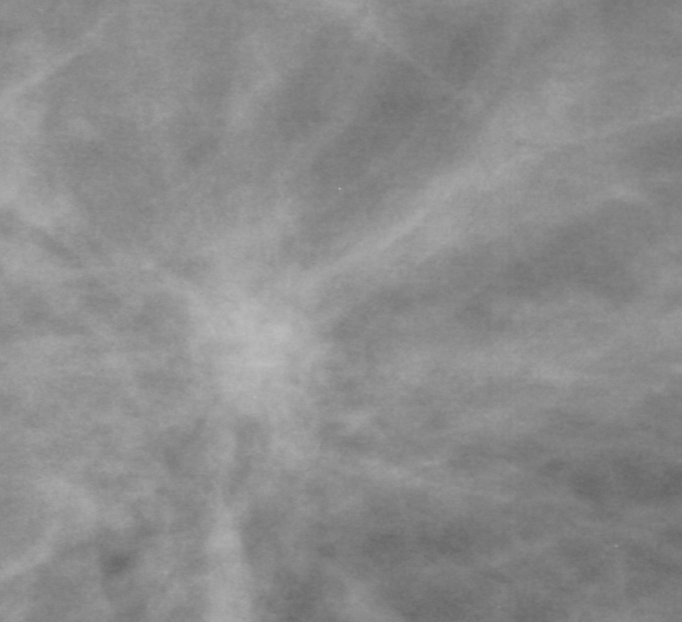

In our experiments, we use the Digital Database for Screening Mammography (DDSM) [4], a collaboratively maintained public dataset at the University of South Florida. It comprises approximately 2500 studies each containing both mediolateral oblique (MLO) and craniocaudal (CC) views of each breast. Each image is grayscale and accompanied by a mask specifying the region of the pre-segmented mass if present. Examples of benign and malignant masses are shown in Fig. 1.

Deep learning models often lack interpretability and as such are hard to adopt for practical use in medical settings. [21] describe a methodology to visualize saliency maps which show the regions of an image the network is sensitive to when making predictions. This is performed by computing the gradient of the image with respect to the unnormalized class scores. Regions with larger gradient indicate higher contribution to the prediction (brighter in Fig. 3). Both the AlexNet and GoogLeNet learn to attend to the edges of the mass, which is a high-signal criterion for diagnosis, while also paying attention to context.